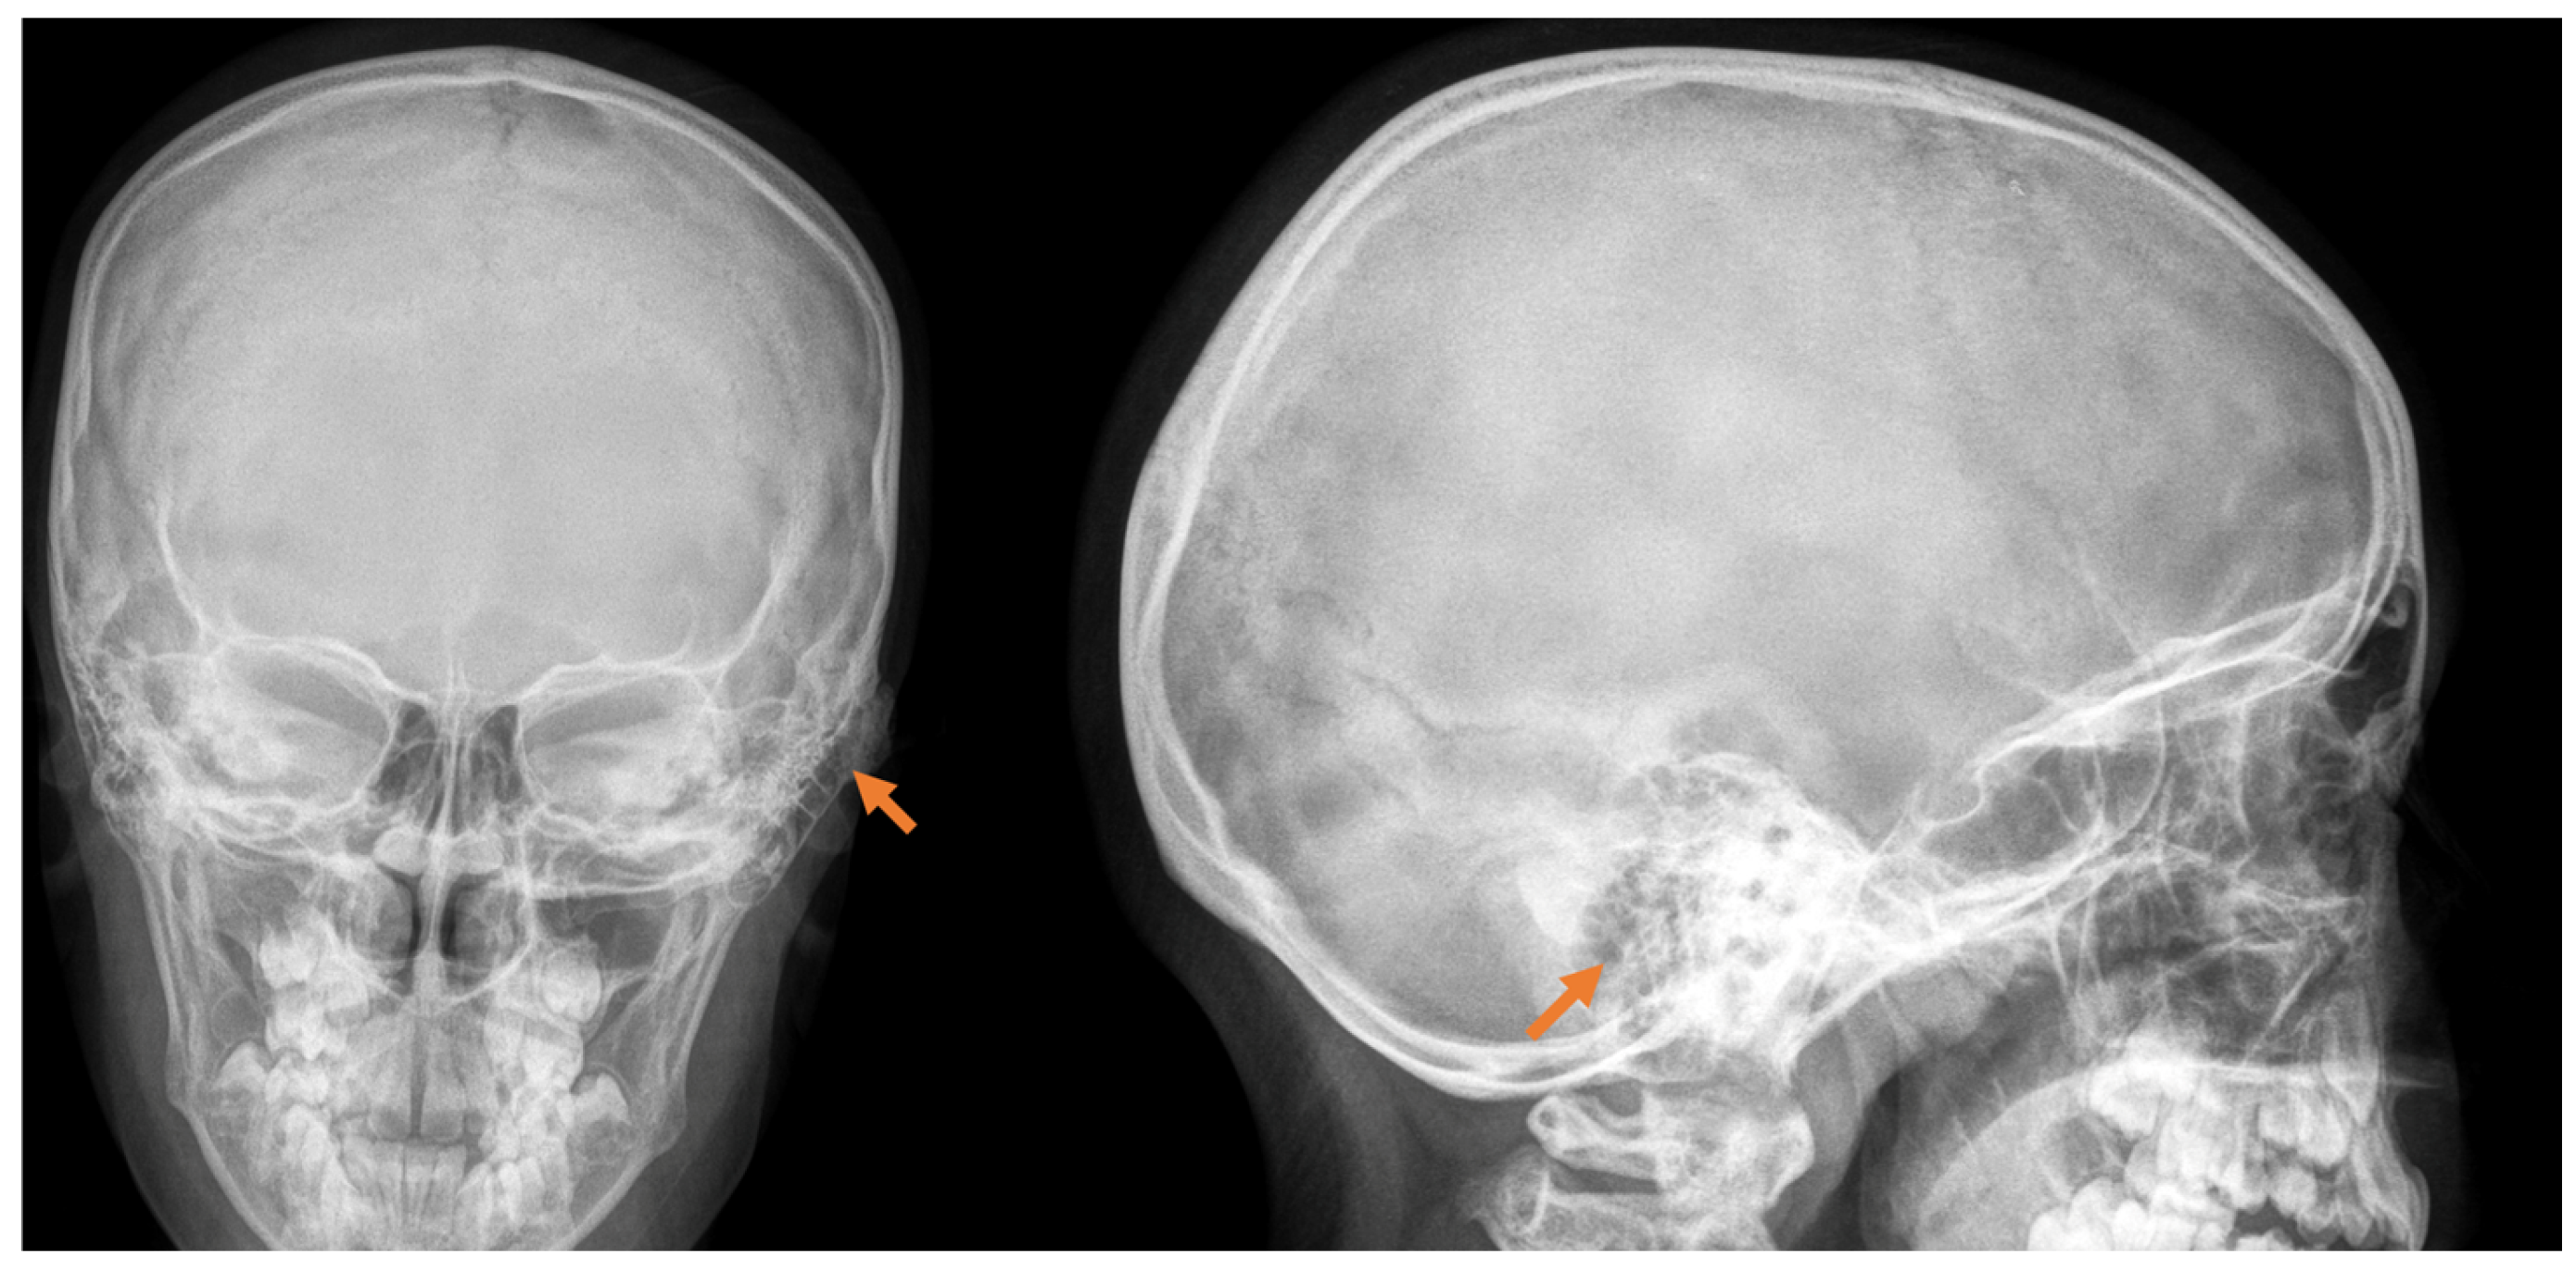

The diagnosis is made by performing a computed tomography scan, with a clear presentation of the size, density, and boundaries of spread (Figure 1). In the presented clinical case, we establish a mastoid process osteoma with slow progression for a period of 6 years, creating only a cosmetic defect in the retroauricular area.

Figure 1.

Radiological examination in front and side view, with the detection of a slight deformation along with bone growth in the cortical area of the mastoid process, pointed with orange arrow.